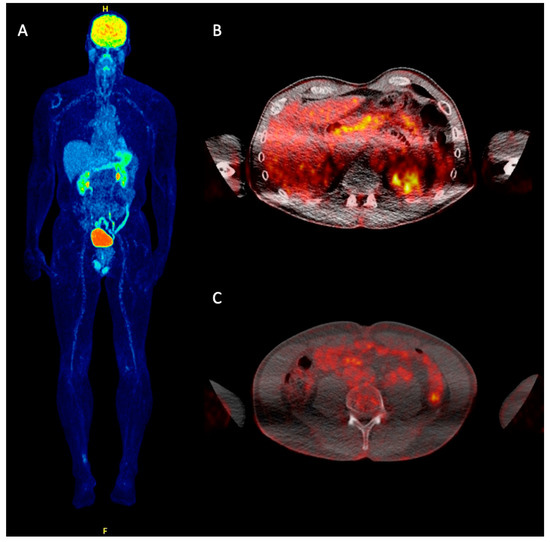

- Eshghi, N.; Lundeen, T.F.; MacKinnon, L.; Avery, R.; Kuo, P.H. 18F-FDG PET/CT for Monitoring Response of Merkel Cell Carcinoma to the Novel Programmed Cell Death Ligand 1 Inhibitor Avelumab. Clin. Nucl. Med. 2018, 43, e142–e144. [Google Scholar] [CrossRef] [PubMed]

- Vellani, C.; D’Ambrosio, D.; Licata, L.; Vacchieri, I.; Bernardo, A.; Trifirò, G. Monitoring response of advanced Merkel cell carcinoma to Avelumab with 18F-FDG PET/CT. Eur. J. Nucl. Med. Mol. Imaging 2018, 46, 1197–1198. [Google Scholar] [CrossRef] [PubMed]